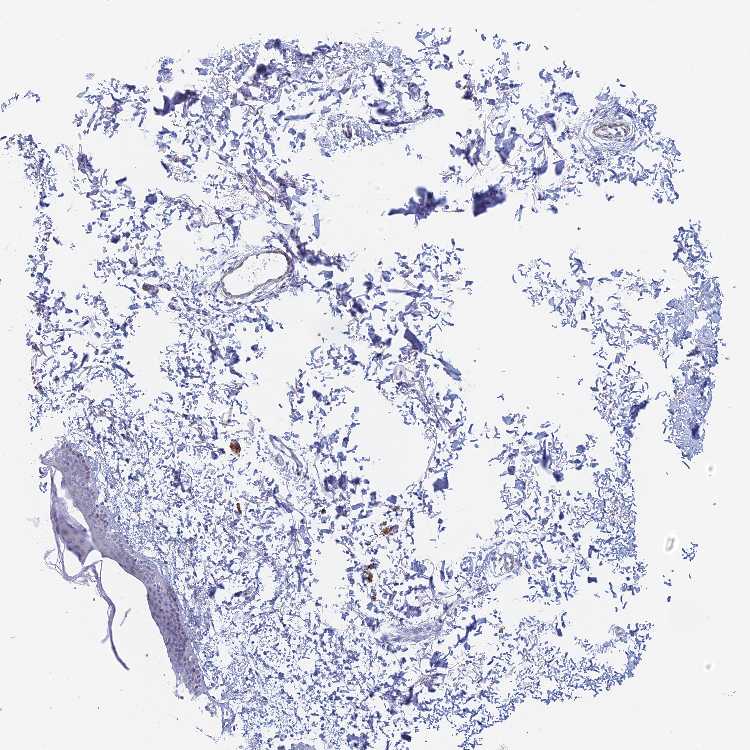

KCNK18